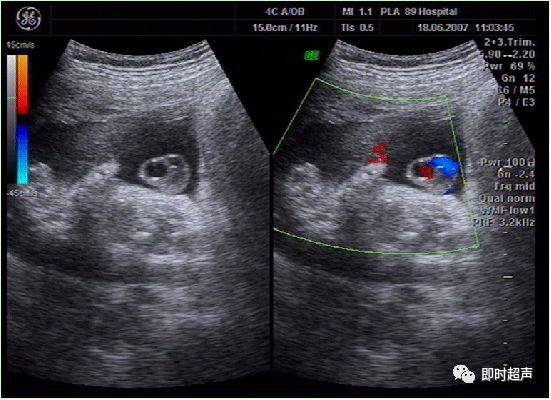

四维彩超发现单脐动脉一例

图片尺寸640x479